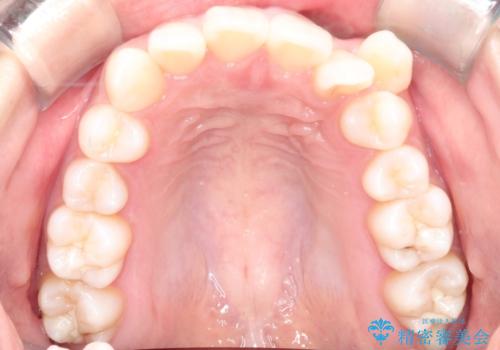

【審美ワイヤー】八重歯を治したい。

- 左上の犬歯の凸凹や正中のずれを主訴に来院されました。

凸凹を治すために、上下左右の小臼歯を抜歯してワイヤー矯正を行いました。